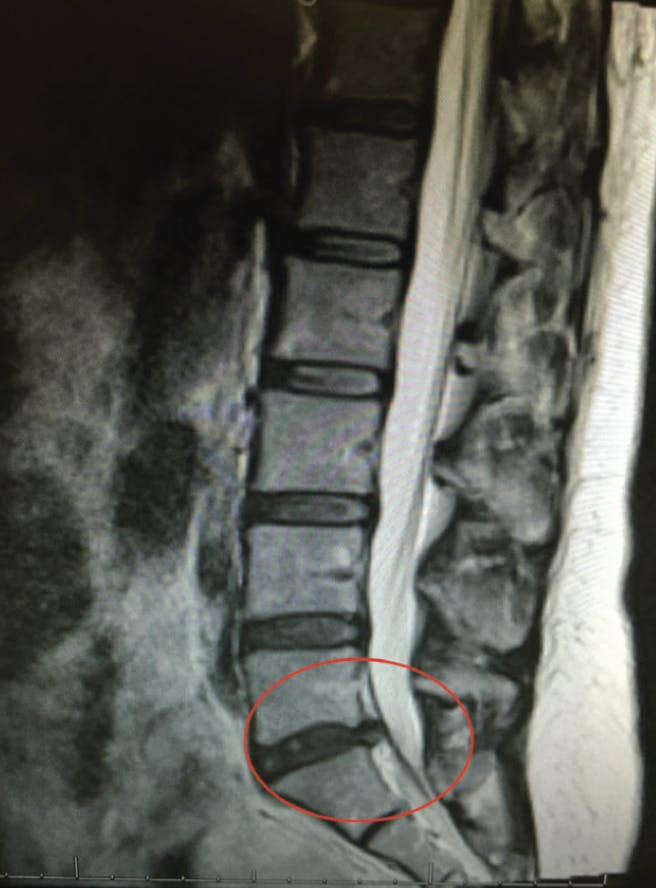

In 2015, I slipped on a puddle of water on the OR floor and fell. I subsequently developed a large L5-S1 disc herniation (Figure 1) that caused severe back pain and progressive weakness in my right leg that prevented me from working or traveling. I saw two neurosurgeons and one orthopedic surgeon, all of whom were ready to operate, but I was not ready to undergo surgery.

Figure 1. An MRI of Dr. Dhaliwal’s spine in December 2015 showing an L5-S1 disc herniation (red circle).